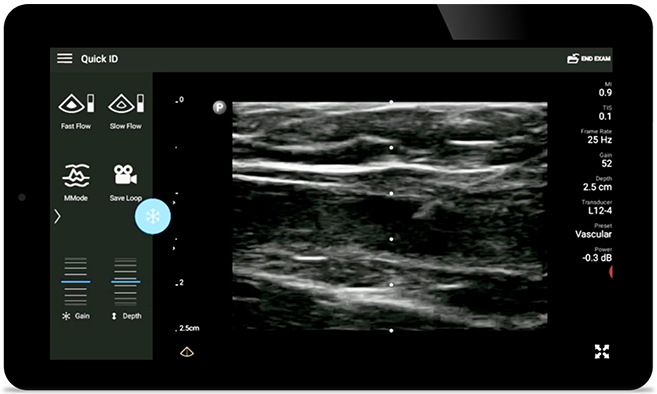

Diminuir complicações de inserções de CVC

A orientação por ultrassom em tempo real pode melhorar a precisão e a segurança das inserções de CVC.

• MHzFaixa de frequência operacional de 1 a 4 MHz • Tamanho da abertura: 34mm • 2D, Doppler colorido e pulsado*, modo M, XRES avançado e diagnóstico com imagem harmônica, SonoCT • Diagnóstico por imagem de alta resolução para aplicações superficiais: tecidos moles, vasculares, superficiais, musculoesqueléticos e pulmonares • Marcador de linha central • Transdutor USB-C com cabo substituível • Disponivel em Android